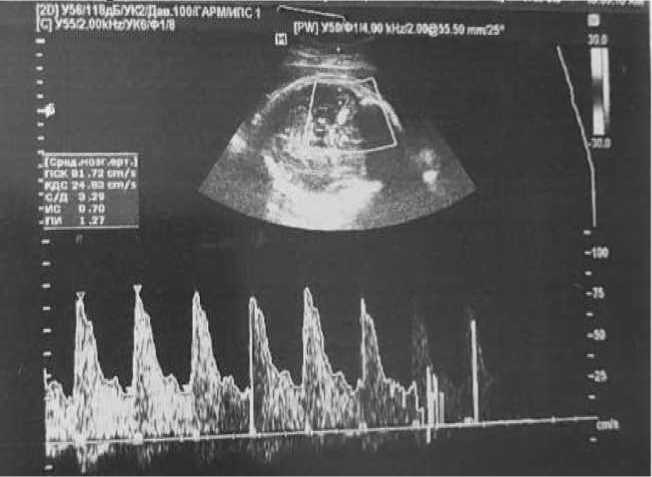

На 28-й неделе беременности пациентка вновь обратилась к врачу-терапевту женской консультации по поводу жалоб на температуру до 39 °C. В ходе сбора анамнеза было выяснено, что в течение последних двух недель была в контакте с больным ребенком (ОРВИ). В ходе АУО было выявлено тазовое предлежание плода. ВПС плода по типу тетрады Фалло, кардиомегалия (гипертрофия миокарда обоих желудочков, умеренное количество жидкости в полости перикарда), двусторонний гидроторакс, асцит. Ультразвуковые признаки неиммунной водянки плода. Осложнения: фетоплацентарная недостаточность. Многоводие (рис. 2).

Рис. 2. Фотофиксация изображений АУО плода на 28-й неделе беременности